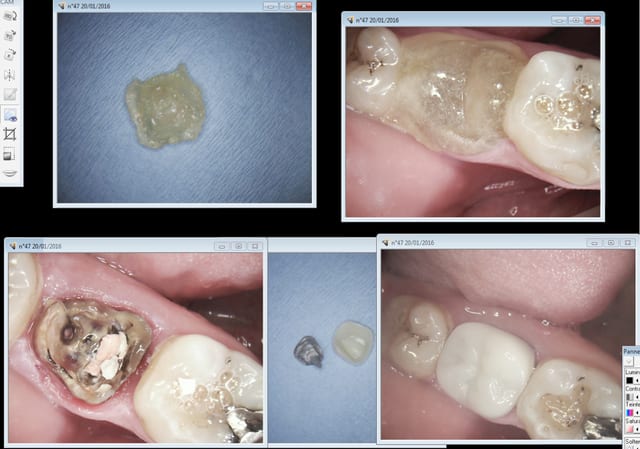

Ici en core + ic provisoire labo sur RTE ( on sort d'une pèche maous costaud) la définitive dans 6 mois.

Capture d e cran 2016 01 20 09.36 - Eugenol

Capture d e cran 2016 01 20 09.37 - Eugenol